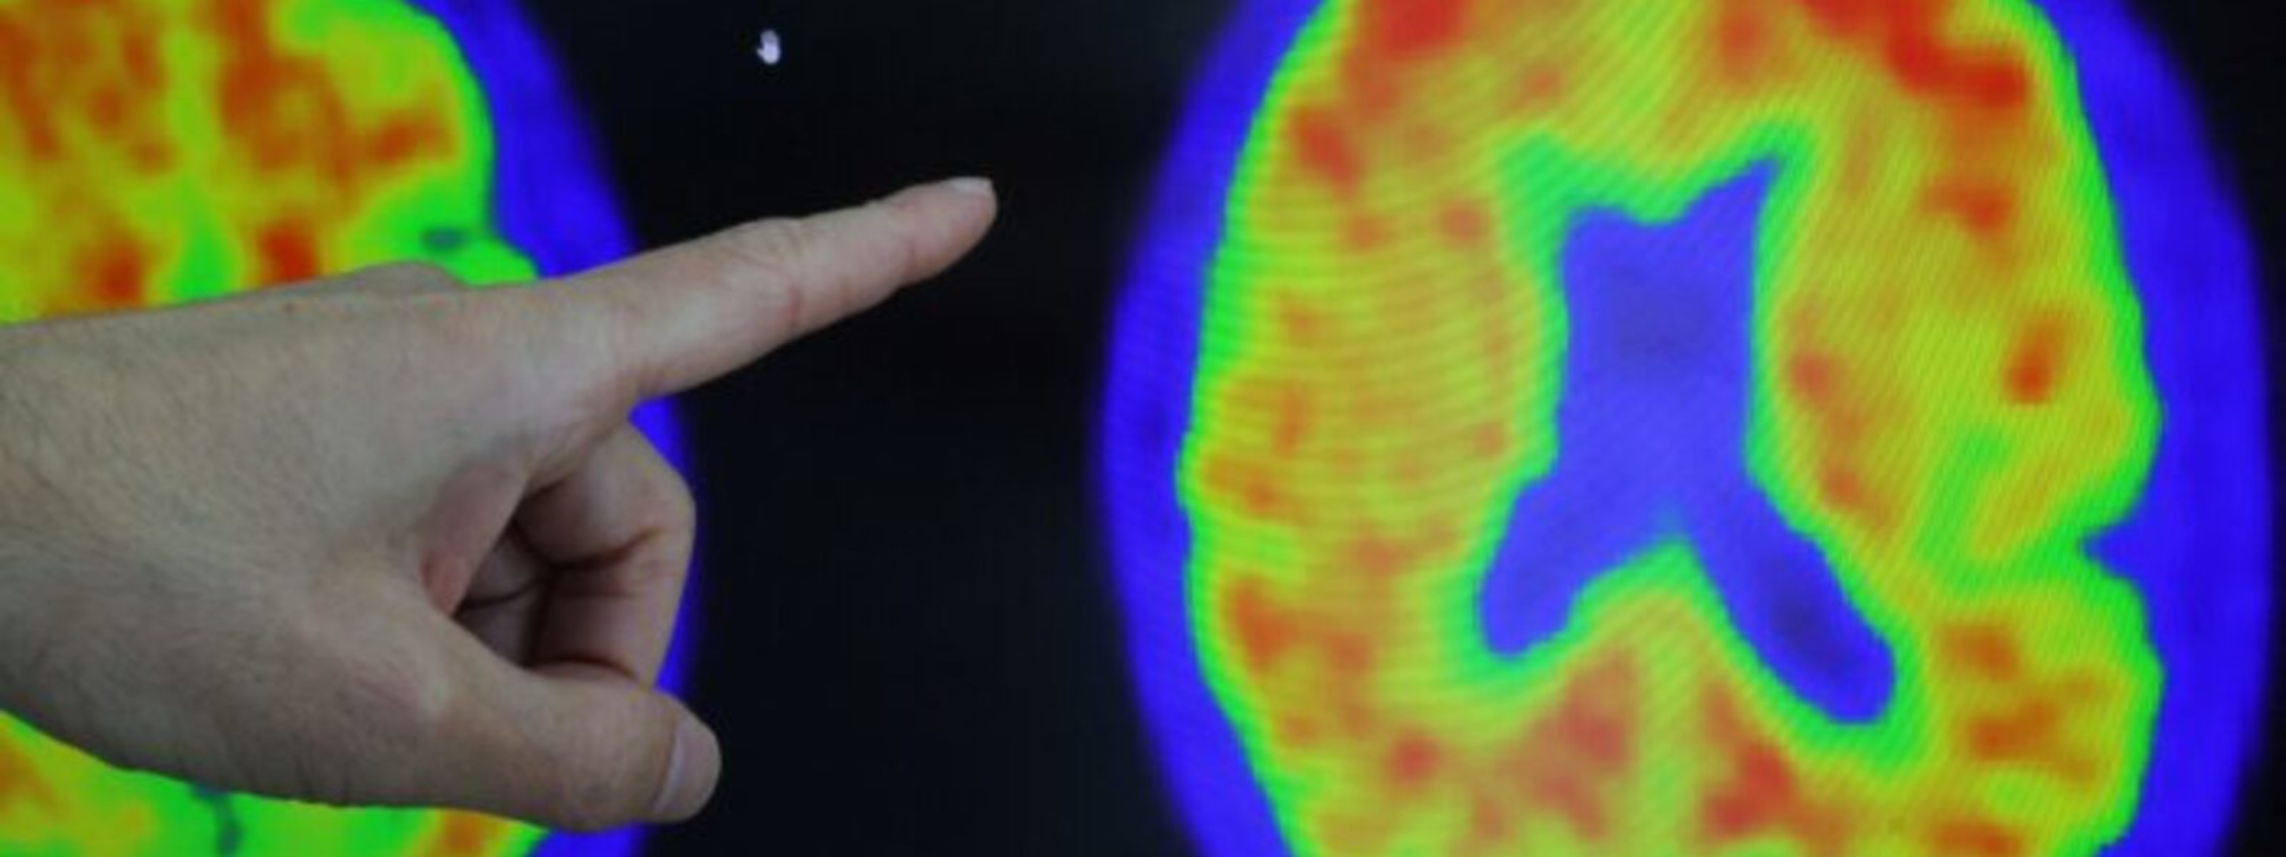

The U.S. Food and Drug Administration (FDA) on Tuesday approved a new Alzheimer’s treatment called donanemab, which could slow progression of the mental disease that impacts millions of Americans, drugmaker Eli Lilly said. The drug, which will be sold under the name Kisunla, is a type of monoclonal antibody infusion that is administered every four weeks and was shown in trials to slow the pace of decline in the early stages of Alzheimer’s. However, the drug presented several significant safety risks, including brain bleeding and swelling, according to a trial released last year. Eli Lilly said the federal health regulator cleared the drug for usage in adults who have early Alzheimer’s disease or mild cognitive difficulties. The drug works by removing amyloid plaques in the brain, which has been associated with the disease....